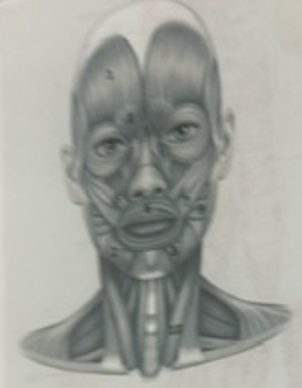

What muscle is 1?

Frontalis

What muscle is 2?

Depressor anguli oris

What muscle is 3?

Depressor labili inferioris

What muscle is 4?

Corrugator supercili

What muscle is 5?

Orbicularis oris

What muscle is 6?

Zygomaticus minor

What muscle is 7?

Zygomaticus major

What muscle is 9?

Buccinator

What muscle is 10?

Sternocleidmastoid

What muscle is 11?

Temporalis

What muscle is 12?

Masseter

What muscle is 13?

Risorius